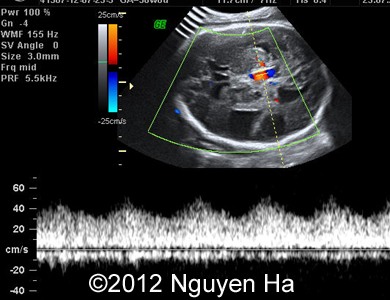

Figure 8-15: 4 days later; image 1-4 suggesting a middle cerebral artery infarction with formation of schizencephaly, no more cortex at the level of the insula.

A 30-year-old woman (G1P0), with unremarkable family history, presented to our unit at 36 weeks of her pregnancy. She did not undergo any previous screening tests. Our examination revealed unilateral hypoechoic inhomogeneous mass within cerebral parenchyma. Our initial diagnosis was teratoma, but repeated exam after four days showed structural changes and different echogenicity of the mass and so our final diagnosis was cerebral hemorrhage. The findings were confirmed by MRI scan.